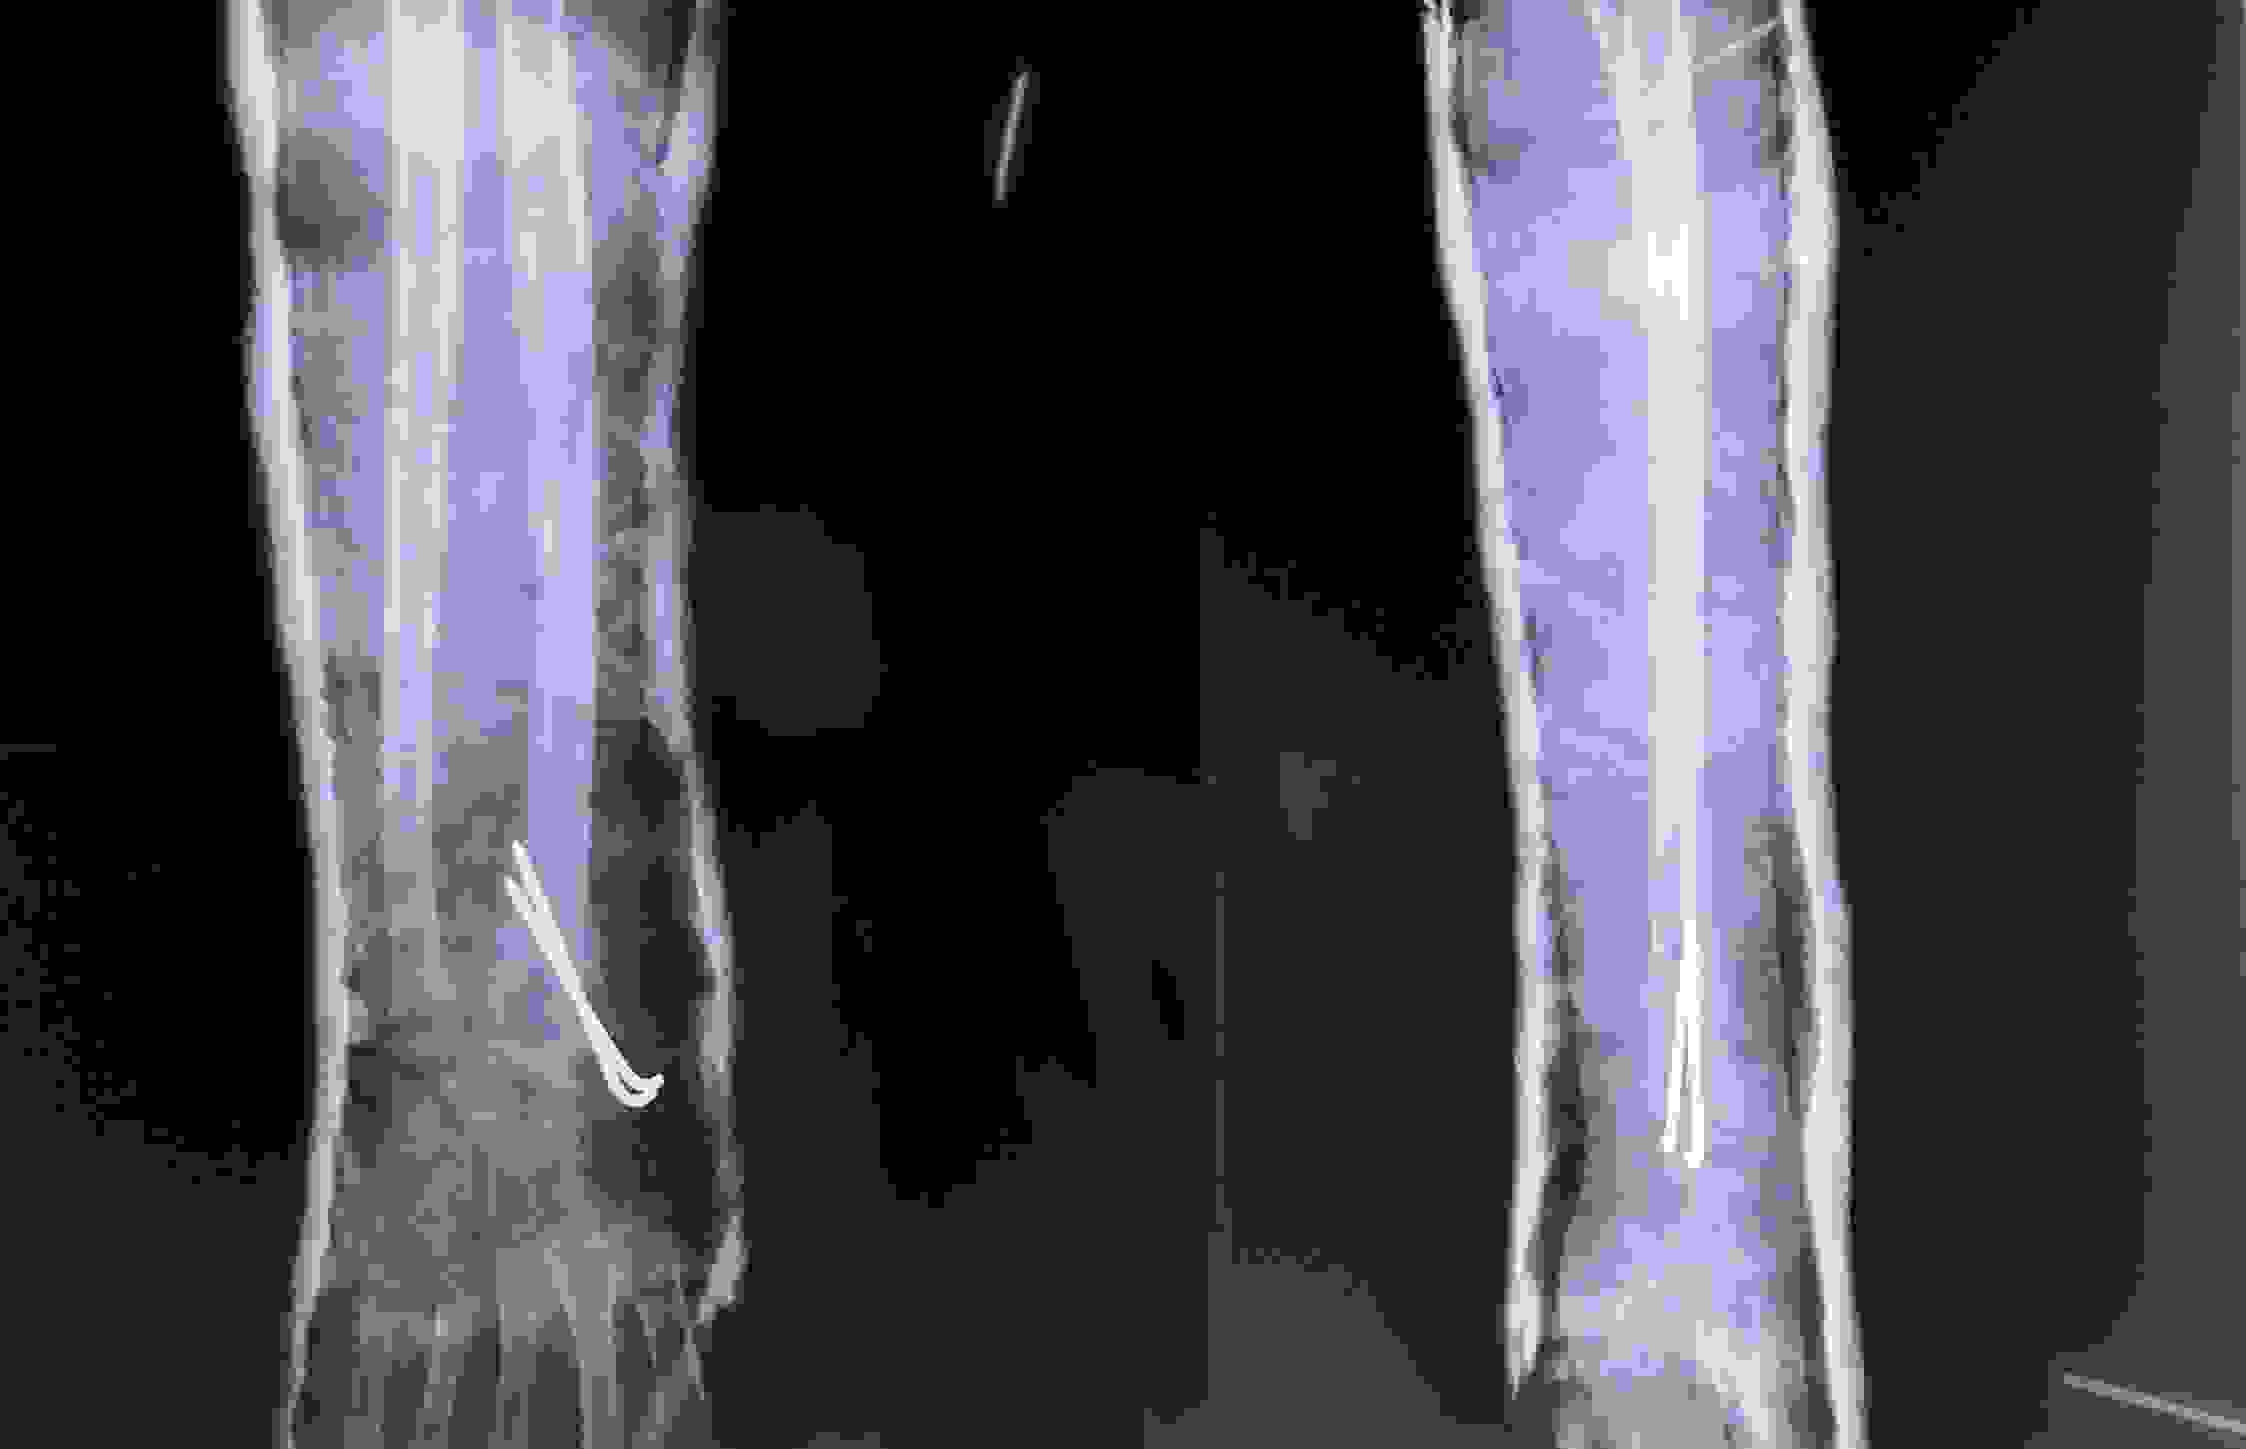

Chấn thương nhi: Gãy đầu dưới hai xương cẳng tay